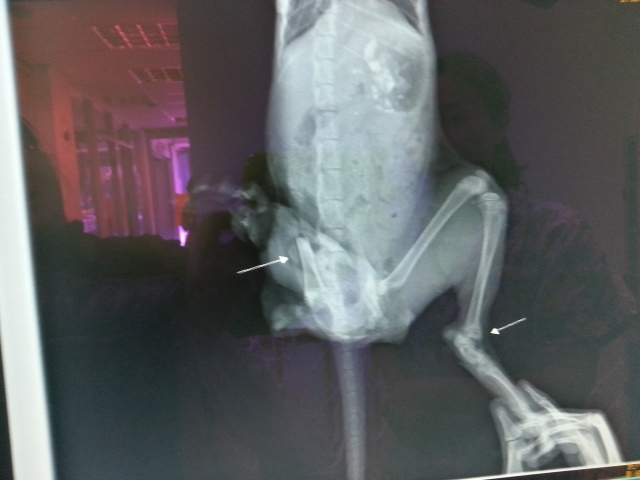

抓到小貓後,這才發現他渾身是傷,

應該是被車子碾過,

右後腿只剩下大腿部份,

鮮血流得滿身…

全身還有多處擦傷,

另一條後腿也破皮、傷口深可見骨!

斷腿部份有些感染,半夜再次進行截除大腿手術。